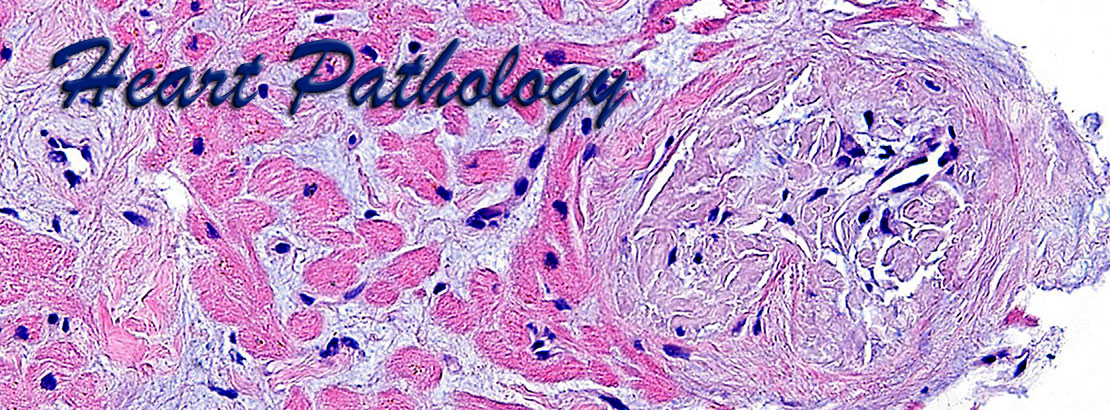

Cardiac pathology is an important area of pathology but is not comprehensively taught at many medical centers due to the paucity of cardiac specimens outside of the autopsy services. Our website uses high definition images obtained from gross pathology specimens and histological slides, both at a resolution of 1800x1350 pixels. Most images have been obtained using Olympus digital cameras.

The images presented here represent a wide variety of heart pathology cases, including acquired diseases, transplantation pathology, idiopathic diseases, tumor pathology, etc., and are accompanied by brief morphological descriptions. The histological images are shown at different optical magnifications and include conventional stains such as hematoxylin-eosin, PAS, trichrome stains, as well as immunohistochemical stains. Also included are some images from normal tissues and from positive and negative controls for the corresponding special stains.